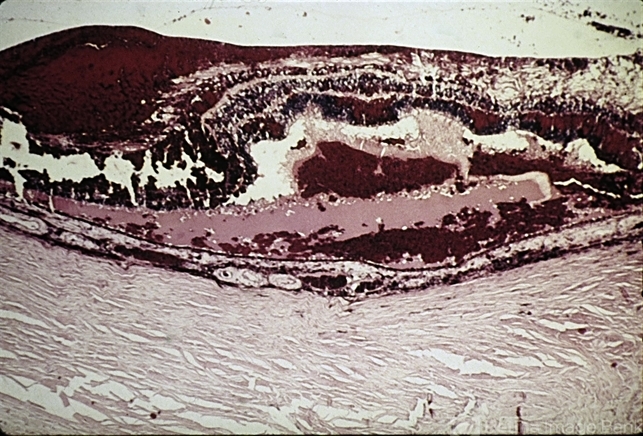

- trauma, hemorrhage

- Severe blunt trauma has produced hemorrhage beneath, in, and in front of the retina.